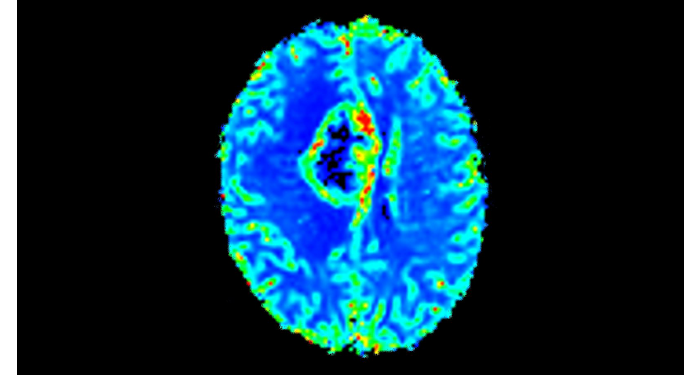

El 70% de los radiólogos consideran que las indicaciones neurológicas son un desafío, sobre todo debido a la falta de técnicas apropiadas de imagenología y visualización¹. Philips tiene como objetivo proporcionar la mejor claridad de diagnóstico posible y orientación terapéutica para todos los pacientes con trastornos neurológicos. Al aprovechar nuestra plataforma digital dStream, este año presentamos un conjunto de estrategias nuevas de imagenología y visualización. Esto puede ayudarlo a resolver preguntas sobre neurología complejas con mayor certeza, así como a desbloquear nuevos territorios neurológicos en aplicaciones neurofuncionales avanzadas. Este es un paso clave para aumentar el diagnóstico neurológico y, en última instancia, impactar más vidas con la RM. ¹ TMTG Market Survey 2016

Nuevas aplicaciones neurológicas